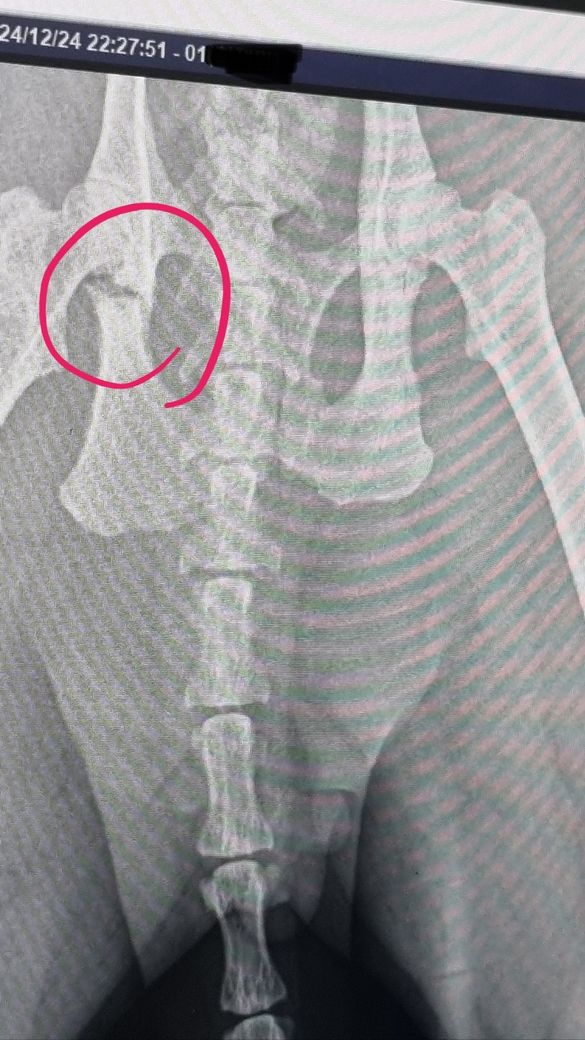

고양이가 고관절이 골절되었는데 병원에서 수술하지 않고 자연스레 붙도록 지켜보자 하는데 이런 경우도 있나요? 수술 해야하는 것은 아닌지 궁금합니다.

원칙적으로 수술을 하는것이 기본입니다. 물론 사진상의 위치에서 고관절의 관절면이 포험되었는지가 예후에 매우 중요한 요소인데, 일부 포함된것으로 보여 수술을 하더라도 예후는 좋지 못할 가능성이 높아 보입니다. 하지만 예후가 좋지 못하더라도 수술을 하지 않았을때가 최악이라면 수술 하는게 차악 수준으로 보아야 하므로 수술을 권장합니다. 수술 가능한 다른 동물병원에 가서 평가 받고 수술진행하시는걸 추천합니다. 원칙상 CT검사를 통한 3차원의 골격 구현 후 평가해야 하는 부분입니다.